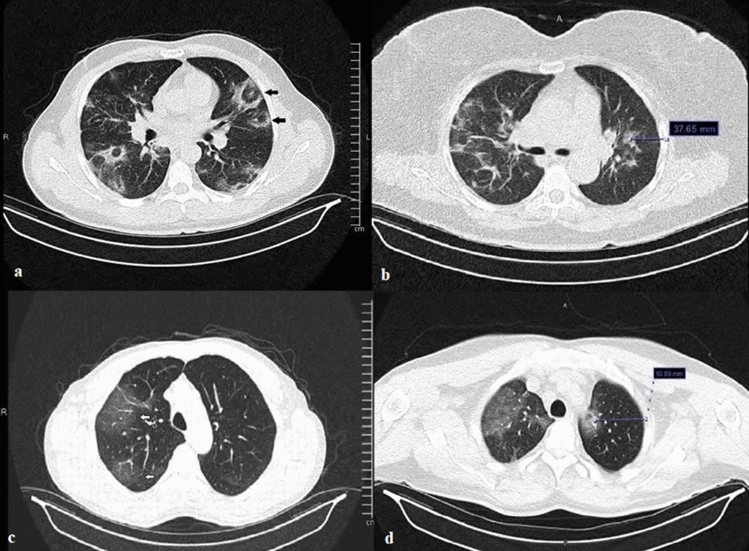

The most common lesions on CT images were ground-glass opacities, crazy paving sign, and consolidation (Table 2) (Fig. 1). The mean LUS score was found to be 19.9 ± 7.6, and the most common findings were pleural line abnormalities and B line abnormalities (Table 2) (Fig. 2). The total CT score was 14.3 ± 5.3, and CT scores categorized by right- and left-side values and lung segments are presented in Table 3.

Fig. 1.

Thoracic CT images of COVID-19-related pneumonia. a Black arrows: halo sign, b non-pleural lesion and distance to the pleura, c white arrows: ground-glass opacities, d non-pleural hilar lesion and distance to the pleura